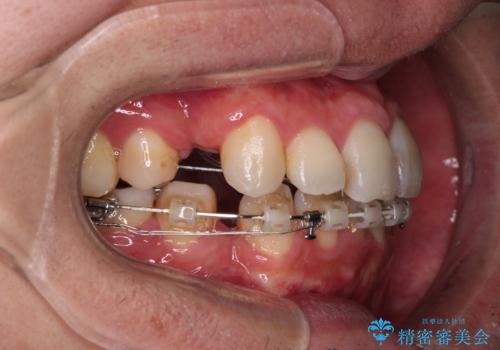

- ハーフリンガル

上下の顎骨が左右に大きくずれており、奥歯が交叉咬合となっていたため、ハーフリンガルよりも表側装置をおすすめしましたが、目立たない装置を強く希望されたため、治療期間が長期化することを前提に、ハーフリンガルにて抜歯矯正を行うこととしました。

裏側装置での交叉咬合改善は非常に困難なもので、頻繁に装置の脱落がありました。

それでも想定以上に治療期間は長期化せず、咬み合わせも口元も満足のいく仕上がりとなりました。